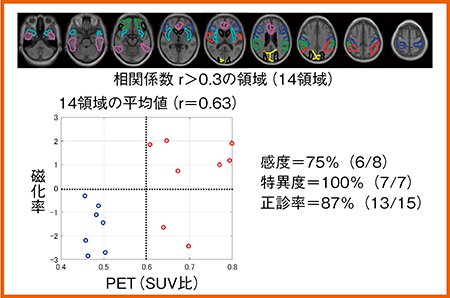

さらに,QSM+VBMと,脳へのAβ沈着を検出するアミロイドPETの比較を多施設共同臨床研究にて行っている。MCIまたはADの患者17名を対象とした解析では,QSM+VBMとアミロイドPETの患者間相関係数が0.3を超える14領域について,磁化率を平均化し,横軸にPET(SUV比),縦軸に磁化率をプロットした。Aβの陽性・陰性のカットオフ値にSUV比0.6を用いた場合,感度75%,特異度100%,正診率87%となった(図4)。

図4 QSMとアミロイドPETの比較